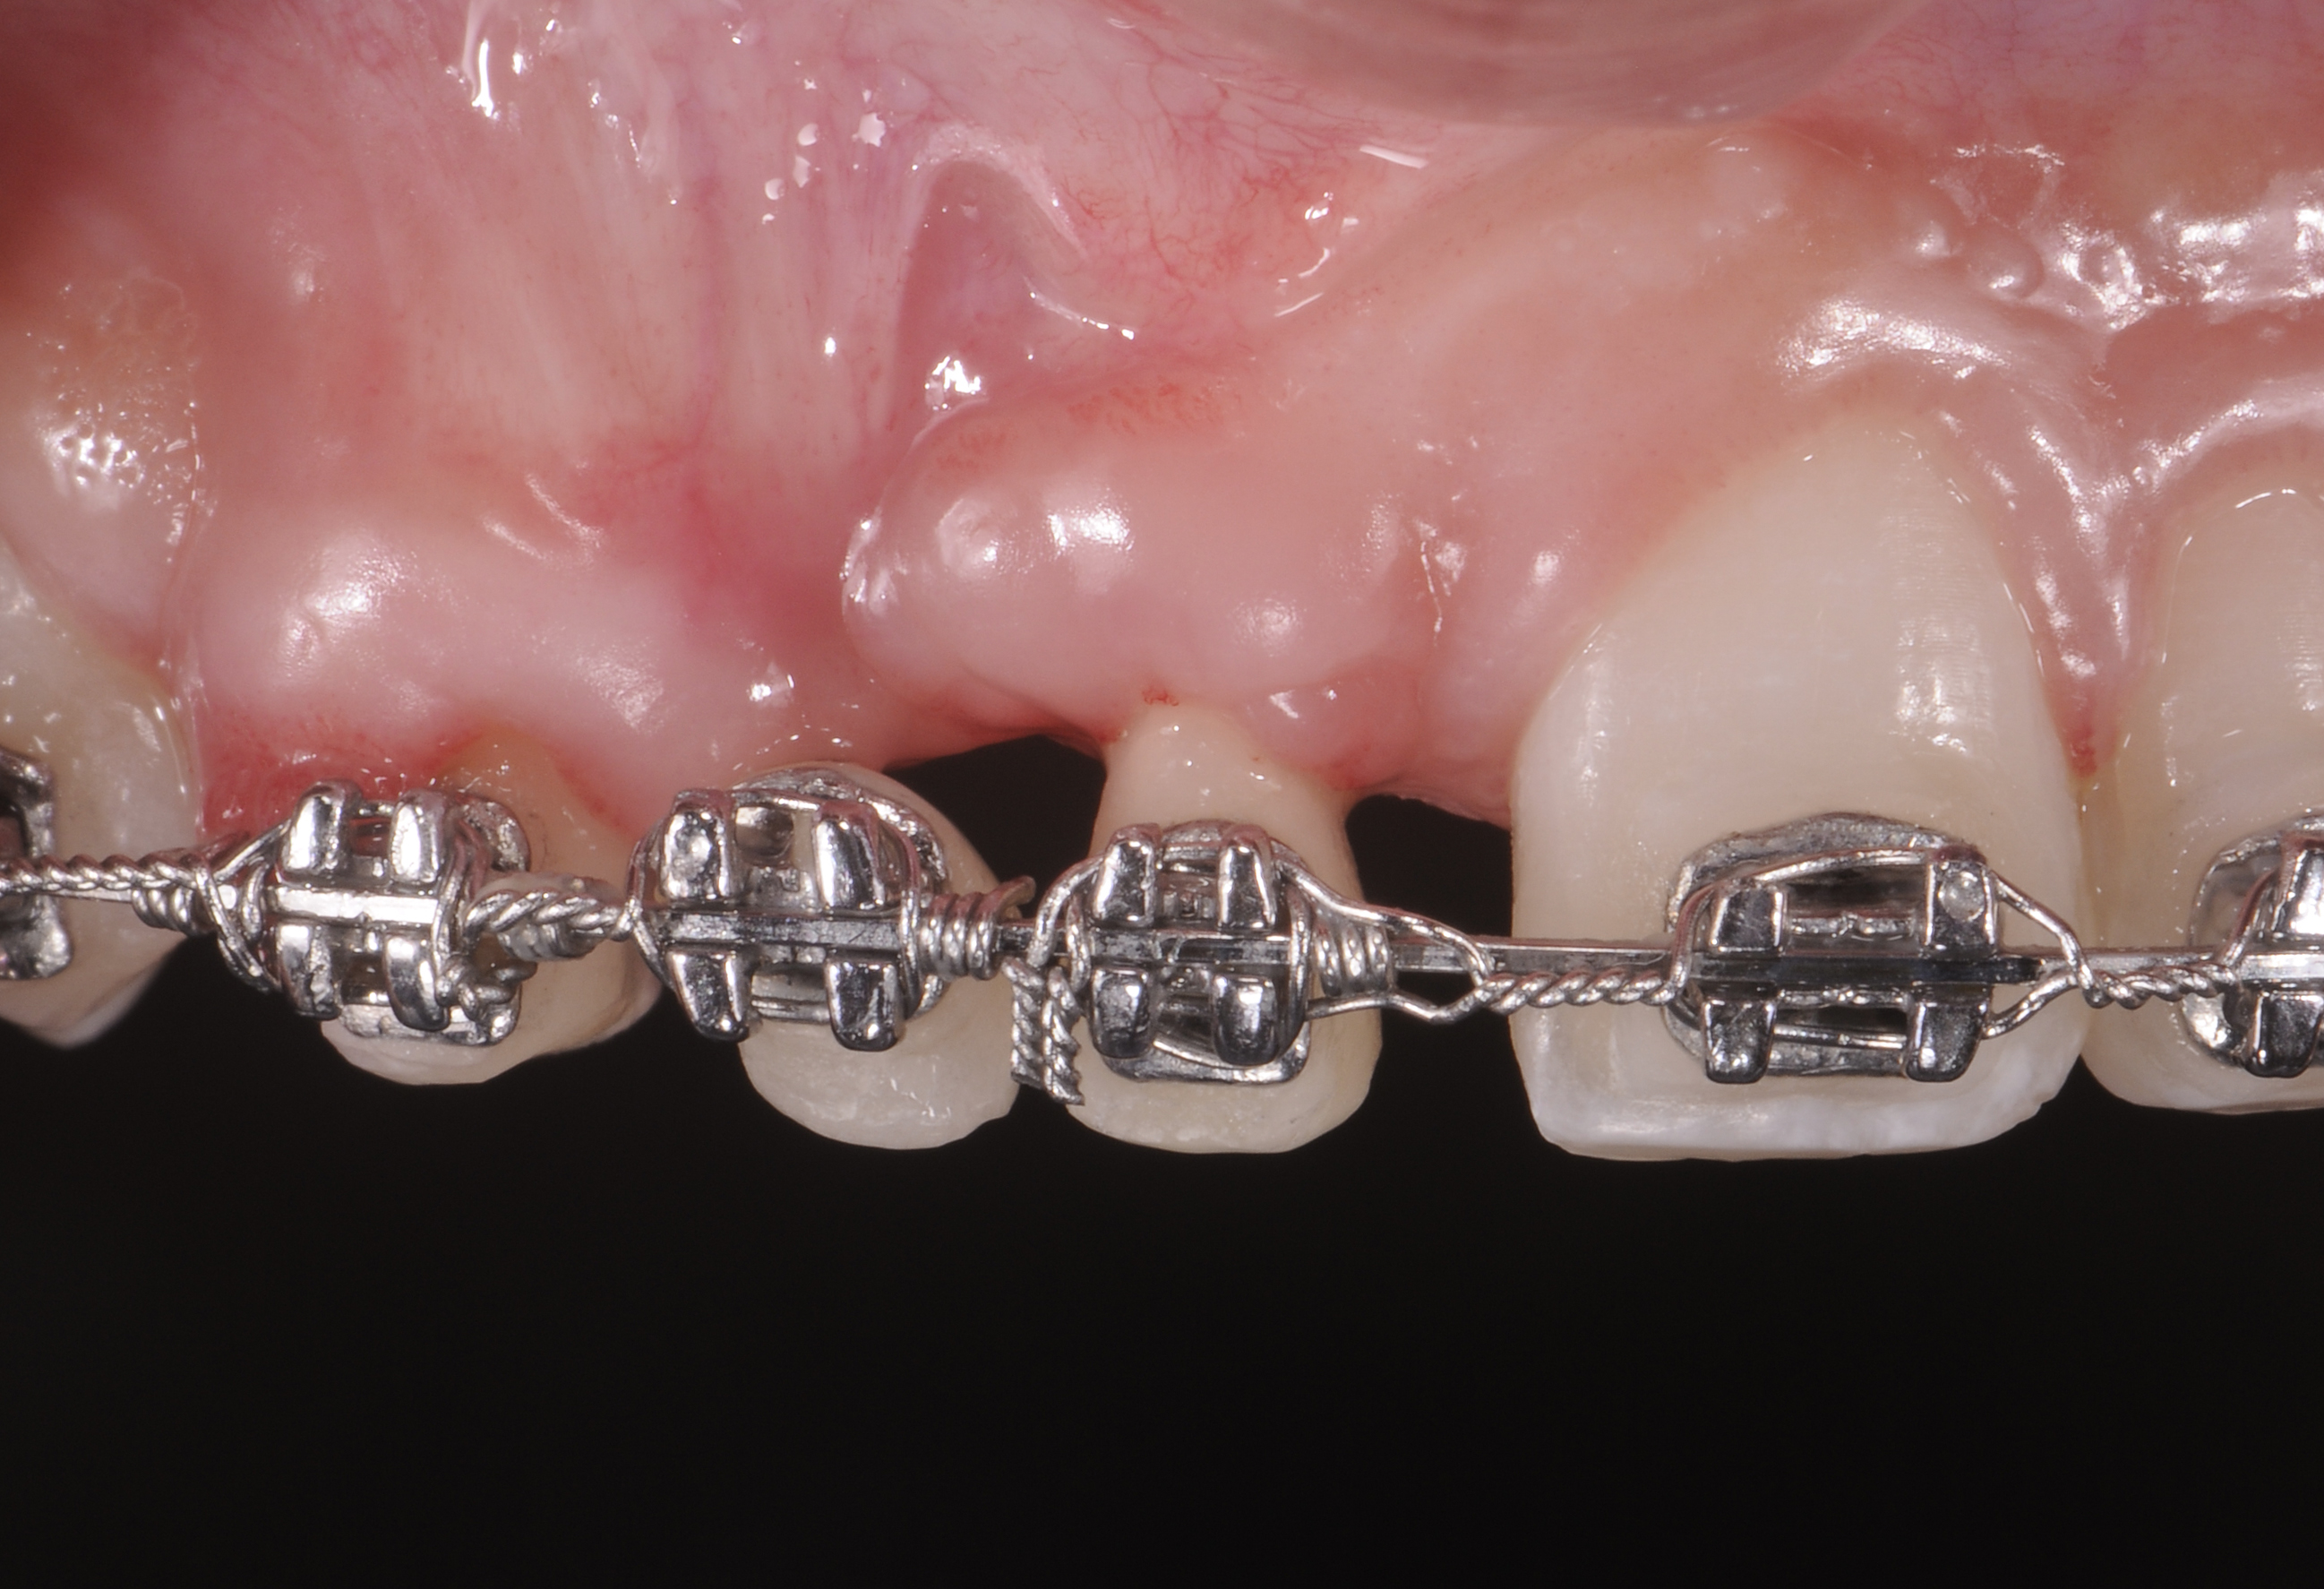

Successful outcomes with forced eruption require the establishment of treatment endpoints, which may include overcompensation beyond the desired soft- and hard-tissue changes. For the present case, achieving ideal gingival-alveolar socket architecture required force-erupting tooth No. 6 to the level of the apical third and tooth No. 8 beyond the confines of its alveolus. As the gingival sulcus is everted through the eruption process, a gingival red patch corresponding to the nonkeratinized sulcular epithelium may appear, as shown around tooth No. 8 in Figure 8 and Figure 9. This tissue will develop into keratinized gingiva when exposed to the oral environment.31,32 Additionally, when forced eruption of this magnitude is performed, there may be a tendency for lingual displacement that needs to be addressed with root-torquing orthodontic auxiliaries (Figure 6 and Figure 7).

When forced eruption is completed, the teeth should be splinted for a 3-month stabilization period,30 which will allow mineralization of osteoid tissue and settling of the gingival remodeling process. The degree of forced eruption in the present case was such that extreme mobility precluded the use of a provisional restoration. Instead, a metal-reinforced direct composite splint extending from teeth Nos. 6 to 8 was fabricated in situ (Figure 8 and Figure 9). When compared with the preoperative condition (Figure 2), Figure 8 and Figure 9 depict the treatment progression with forced eruption. The restoration of adequate alveolar height was achieved while enhancing the soft-tissue architecture, and the everted sulcular epithelium on tooth No. 8 proceeded to develop keratinization. However, the pre-existing defect still manifested itself in the form of a residual cleft.

Fig 6. Eruption of tooth No. 6 to the apical third and tooth No. 8 beyond its alveolus was needed to achieve ideal site development. This degree of forced eruption often results in lingual displacement that needs to be managed with root-torquing auxiliaries. Sulcular epithelium eversion can be observed on tooth No. 8.

Figure 6

Fig 7. Eruption of tooth No. 6 to the apical third and tooth No. 8 beyond its alveolus was needed to achieve ideal site development. This degree of forced eruption often results in lingual displacement that needs to be managed with root-torquing auxiliaries. Sulcular epithelium eversion can be observed on tooth No. 8.

Figure 7

Fig 8. Compared to the preoperative view seen in Fig 2, adequate alveolar height and gingival profile were achieved with forced eruption (Fig 8). Direct composite splint would remain for 3 months. Residual cleft was a visible remnant of iatrogenic defect. Post-orthodontically, keratinization of sulcular epithelium on tooth No. 8 was evident (Fig 9).

Figure 8

Fig 9. Compared to the preoperative view seen in Fig 2, adequate alveolar height and gingival profile were achieved with forced eruption (Fig 8). Direct composite splint would remain for 3 months. Residual cleft was a visible remnant of iatrogenic defect. Post-orthodontically, keratinization of sulcular epithelium on tooth No. 8 was evident (Fig 9).

Figure 9